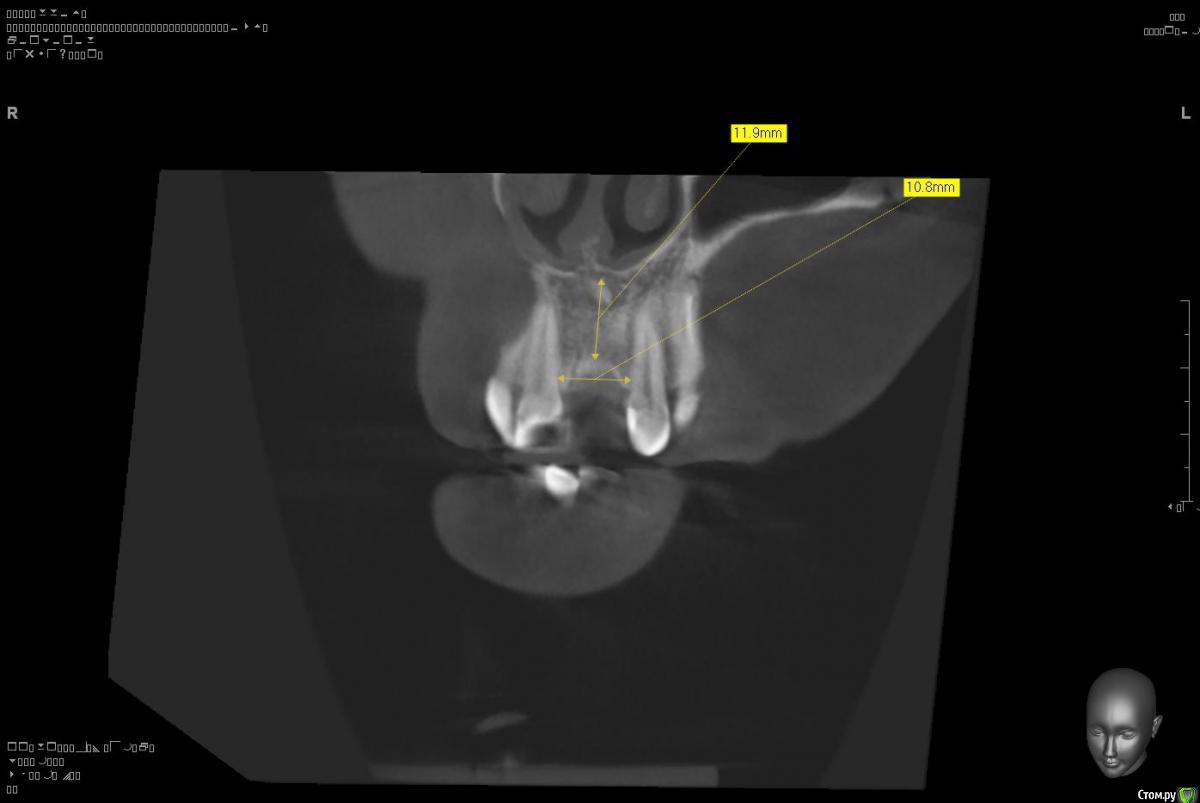

Platon Опубликовано 10 января, 2016 Поделиться Опубликовано 10 января, 2016 Здравствуйте.Помогите с планированием начинающему.Пациентка 38 лет. отсутствует 21. визуально в области 21 провал (фото нет, пока только кт). ходит с акриловой "птичкой"ортопед говорит: ставь, она к эстетике не будет предъявлять претензий))). с чем мне не хочется соглашаться(система ALPHA BIOкак правильно поступить?какие варианты рассматриваю:1. имплантация 3,75 на 11.5 SPI. ,+ временная коронка. Без какой либо пластики.2. костная пластика (мембрана,ксено,) без имплантации, сст, капа на 4 -6мес. потом имплантация + временная коронка3. имплантация, сст , временная коронка С учетом обстановки, прессинга, отсутствия опыта в аугментации, склоняюсь к третьему варианту. заранее спасибо за советы!удачного дня! Ссылка на комментарий

Platon Опубликовано 31 января, 2016 Автор Поделиться Опубликовано 31 января, 2016 Продолжение.не судите строго за фото, первый раз вообще фоткаю операцию)спасибо за советы.По порядку. После того, что мне написали, я решил все -таки уговорить на конусный имплантат (3.7-11.5 ImplantDirect). Также ортопед не хотел делать временную коронку, сказал что сделает каппу, птичку в топку -тоже сделали. Слизистая в области 21 была в рубцах. Исходя из этого всего я решил, коль временной коронки не будет, то сст подсаживать тоже не стану пока,(ортопеда уговаривал сделать временную коронку)))- торк был хороший 35-50н) для того чтобы сст попрактиковаться, но(((.в итоге, анестезия, разрез, сверло пилотное и сверло 2.2, далее расщепление с помощью набора майзенгер с использованием спредеров до нужного диаметра, установил имплантат, торк контролируемый, можно было подобрать любой) в итоге оставил 35. заглушка, совсем немного ксено, мембрана, ушился. ждем. Будет что-то типо каппы которая слегка отдавливает десну,формируя сосочки. не знаю, ни разу такую еще не видел.планирую на этапе раскрытия все-таки сст и временную коронку увидеть.вот. через 4 мес. выложу, что получилось) Если есть советы, критика, всему буду рад, спасибо 3 Ссылка на комментарий